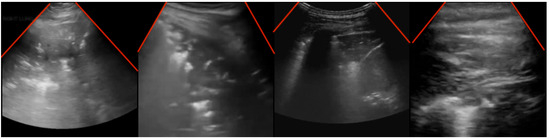

As explained in Section 4, to confirm the viability of the COVID-Net L2C-ULTRA prediction results, we apply GSInquire [38] to the ultrasound image inputs. Our contributing clinician (A.F.), who possesses expertise in ultrasound image analysis, randomly reviewed the outcomes of GSInquire annotation and reported his findings and observations. This assessment aimed to determine whether the network effectively and reliably captures clinically important patterns. Our contributing clinician (A.F.) is an Assistant Professor in the Department of Emergency Medicine, and serves as the ultrasound co-director for undergraduate medical students at McGill University. He is practicing Emergency Medicine full-time at Saint Mary’s Hospital in Montreal. He was provided with the results of the proposed model on test set to confirm its validity. Of the images reviewed, four examples, shown in Figure 7, were chosen as examples to demonstrate the model’s performance on COVID-19, pneumonia, and normal annotated images. The summary of our expert clinician’s report is as follows.

Case 1 (Figure 7a). This image demonstrates the presence of b-lines throughout the scanned window which is assumed to be an intercostal space. The pleura appears to be broken and irregular and there is a suspicion of subpleural consolidations. In the appropriate clinical context, this appearance would be one of the classic lung ultrasound presentations of COVID-19.

Case 2 (Figure 7b). In this image, it is not very clear what GSINquire is focusing on and another frame from this clip would be needed to make a better interpretation. Nevertheless, the pleural and subpleural region emerges as the pivotal element. Considering the peripheral location of COVID-19 lesions within the lungs, this area precisely aligns with our anticipation of locating pathological indicators.

Case 3 (Figure 7c). This image denotes lung hepatization and a classic appearance of consolidated lung, which is a feature of pneumonia.

Case 4 (Figure 7d). This image denotes the classic appearance of the lung on ultrasound with the presence of the pleura and the artifacts called a-lines, which are present in normal lungs.

The observations and findings from our expert clinician substantiated the presence of pertinent artifacts and markers associated with lung diseases, such as consolidations and b-lines, along with indicators of healthy lungs, confirming the reliability of COVID-Net L2C-ULTRA in capturing clinically relevant features.

Figure 7. Sample ultrasound images, annotated by GSInquire, reviewed and reported on by our contributing clinician. (a) COVID-19 example; (b) COVID-19 example; (c) pneumonia example; (d) normal example.